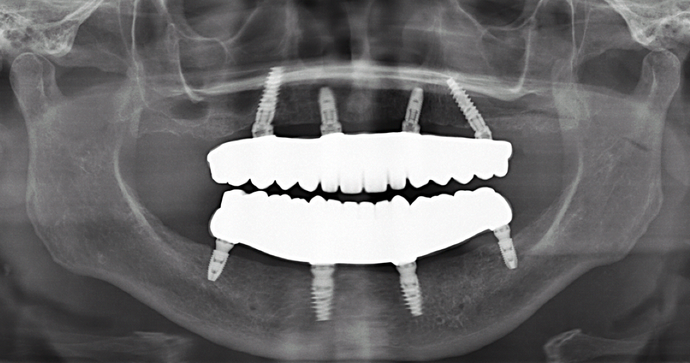

Patient had severe gum disease and she started losing her teeth one by one and was very unhappy with her partials. Patient was holding on to the very last few teeth in her mouth which were loose, in order to avoid wearing dentures! When she discovered Dr Bidra, and was informed that she could get transformed in one single day, she and her husband were immediately motivated. Patient had her teeth extracted, implants placed and new teeth installed all in one day.

Procedures : extractions, implants, All on 4 , Teeth in a day, no bone grafting and full mouth reconstruction with monolithic zirconia bridges.